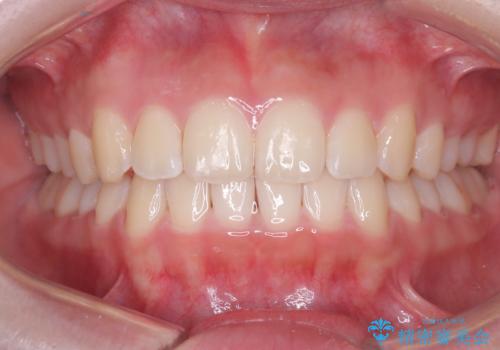

下の前歯のがたつきは解消され、滑らかなアーチ状の歯並びとなりました。

目立たずに治療が進んだことに対しても、患者様から高い満足のお声をいただきました。